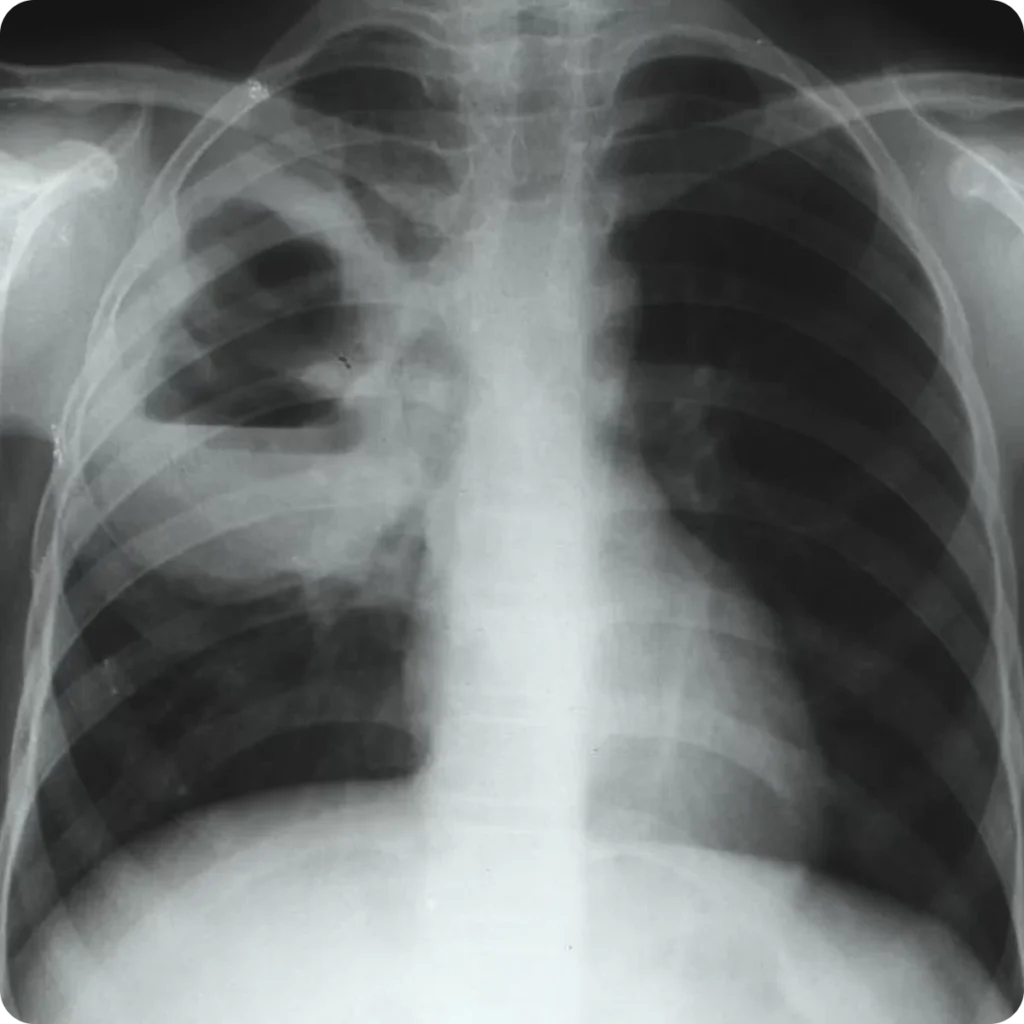

- Evaluación Radiológica: Las radiografías de tórax o tomografías computarizadas pueden mostrar imágenes típicas de neumonía necrotizante, abscesos pulmonares o empiema. La presencia de cavitaciones en las imágenes es particularmente sugestiva de una infección anaeróbica.

En el diagnóstico de infecciones pleuropulmonares anaeróbicas, la imagenología juega un papel crucial para diferenciar entre las distintas manifestaciones radiográficas de estas infecciones. Los estudios de imagen permiten visualizar las características específicas de cada tipo de infección, lo que ayuda a confirmar el diagnóstico y guiar el tratamiento. A continuación, se describen las características radiográficas típicas de las infecciones pleuropulmonares anaeróbicas y cómo se utilizan las técnicas de imagen para diferenciarlas de otras patologías pulmonares:

1. Absceso Pulmonar:

- Apariencia Radiográfica:

- Un absceso pulmonar típicamente se presenta como una cavidad solitaria con pared gruesa en el pulmón. Esta cavidad está rodeada por una zona de consolidación del tejido pulmonar.

- La cavidad suele mostrar un nivel de aire-líquido, que es una indicación de que hay pus dentro de la cavidad y que la cavidad está parcialmente llena de líquido.

- Diagnóstico Diferencial:

- Es esencial excluir otras causas de enfermedad pulmonar cavitaria, que pueden tener una apariencia similar en las imágenes radiográficas. Estas incluyen:

- Tuberculosis: Los abscesos tuberculosos tienden a ser más múltiples y ubicarse a menudo en los lóbulos superiores.

- Micología: Infecciones fúngicas pueden presentar cavitaciones, a menudo con características específicas según el hongo.

- Cáncer: Los tumores pulmonares malignos pueden formar cavidades, y a menudo tienen bordes más irregulares.

- Infarto Pulmonar: Las áreas de infarto pueden presentar cavitación, pero suelen estar asociadas con antecedentes de tromboembolismo.

- Nódulos Necrobióticos en Artritis Reumatoide: Estos pueden parecerse a abscesos pero suelen estar asociados con una historia de artritis reumatoide.

- Vasculitis Pulmonar: Puede presentar cavitación pero se acompaña de otros hallazgos clínicos y radiográficos asociados con la vasculitis.

2. Neumonía Necrotizante:

- La neumonía necrotizante se caracteriza por la presencia de múltiples áreas de cavitación dentro de un área de consolidación. A diferencia de un absceso pulmonar solitario, hay varias cavidades dentro de una región extensa afectada del pulmón.

3. Empiema:

- El empiema se caracteriza por la acumulación de líquido purulento en la cavidad pleural. En las radiografías, puede parecer como una opacidad en la región pleural que puede ocupar una parte o la totalidad de la cavidad torácica.

- El líquido pleural purulento puede acumularse alrededor de las lesiones pulmonares subyacentes, como abscesos o áreas de neumonía necrotizante.